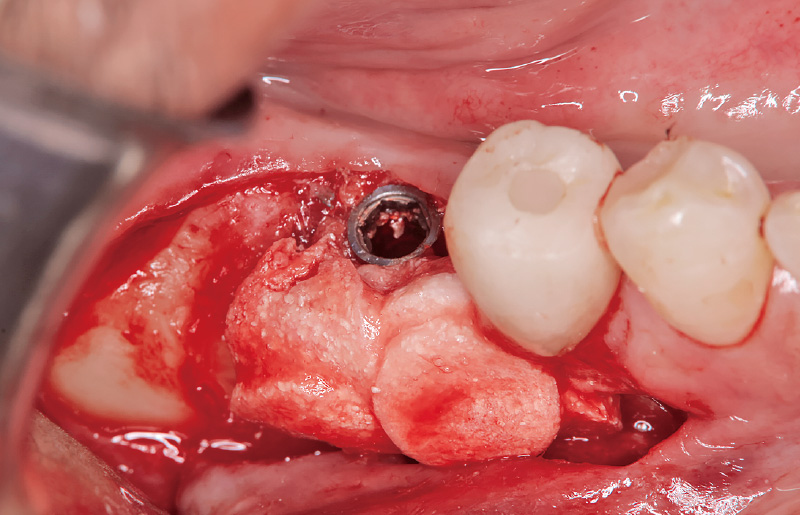

図4 「歯石除去」モードを用い、インプラント体に非接触でデブライドメントを行った。マイクロスコープ下の拡大視野において、一層のインプラント表面を慎重に削り取るイメージで処置を行うことが重要であり、拡大視野による精密操作が治療の成否を左右する。 -

図5 インプラント周囲炎により硬化性骨炎が生じ、骨への血液供給が期待できないため、デコルチケーションを施行した。その際、骨温度の上昇は4℃に留まり、熱による損傷は認められない。 -